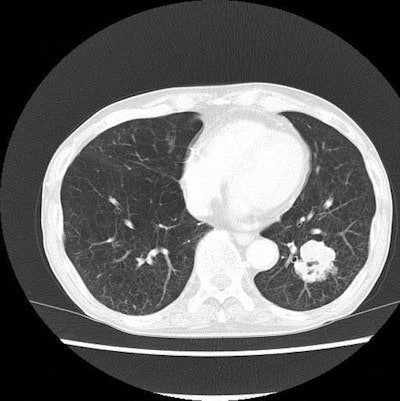

A pair of lung CT images of a patient with emphysema and lung cancer. Above, the image obtained with filtered back projection looks noisy. Below, the image produced with iterative reconstruction has improved noise profile while preserving the anatomical detail, which contributed to radiation dose reduction. Images courtesy of Dr. Takeshi Kubo.The most notable change is the increased awareness of radiation dose among radiographers/technologists, who have been diligently working with radiologists to modify the scan parameter, Kubo added. Education is most important to secure patient safety, and without a sound understanding of the relationship between image quality and diagnostic yield, patients may fail to benefit fully from the advanced technologies.

Iterative reconstruction also can lower radiation dose. Iterative reconstruction involves calculating projection data from reconstructed images, taking into account the effect of the scanner's physical properties. The calculated projection data are compared with measured projection data to correct projection data. The process is repeated to attain the final reconstruction images.

"With this method, higher CT image quality can be obtained with the same scan parameters," the authors noted. "Therefore, radiation dose reduction is possible without compromising the image quality."